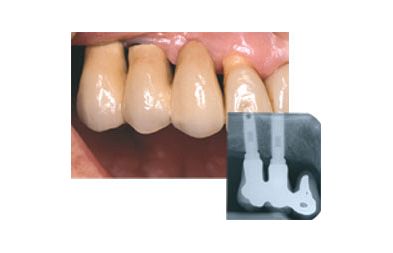

Der kan isættes to eller flere implantater. Disse fungerer som kunstige tandrødder, hvorpå der kan sættes en bro.

Broen sidder fast, og der er igen tænder at tygge med.